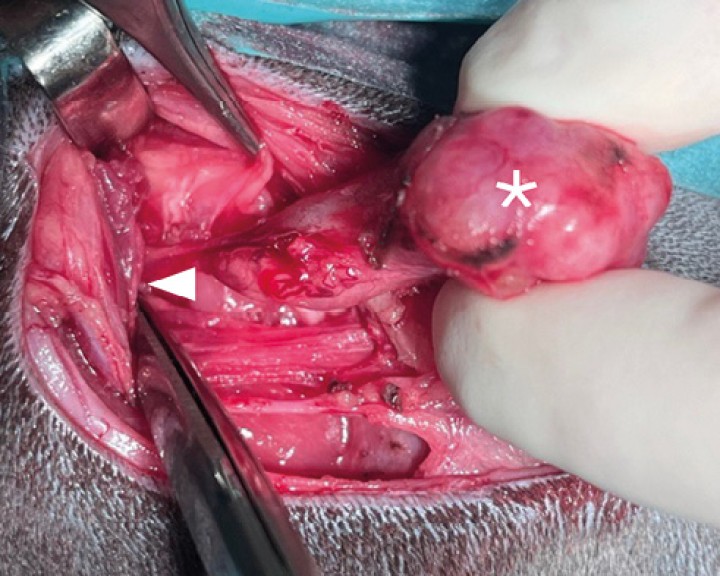

Disección roma de las ramas maxilar ( * ) y linguofacial ( &gt; ) por el aspecto lateral de la glándula mandibular y de la vena yugular externa (estrella) en el aspecto caudal de dicha glándula y linfonodos mandibular (flecha) y retrofaríngeo medial. Ante la sospecha de neoplasia de glándula salivar se realiza excisión del linfonodo para estadiaje.

Disección roma de las ramas maxilar ( * ) y linguofacial ( > ) por el aspecto lateral de la glándula mandibular y de la vena yugular externa (estrella) en el aspecto caudal de dicha glándula y linfonodos mandibular (flecha) y retrofaríngeo medial. Ante la sospecha de neoplasia de glándula salivar se realiza excisión del linfonodo para estadiaje.